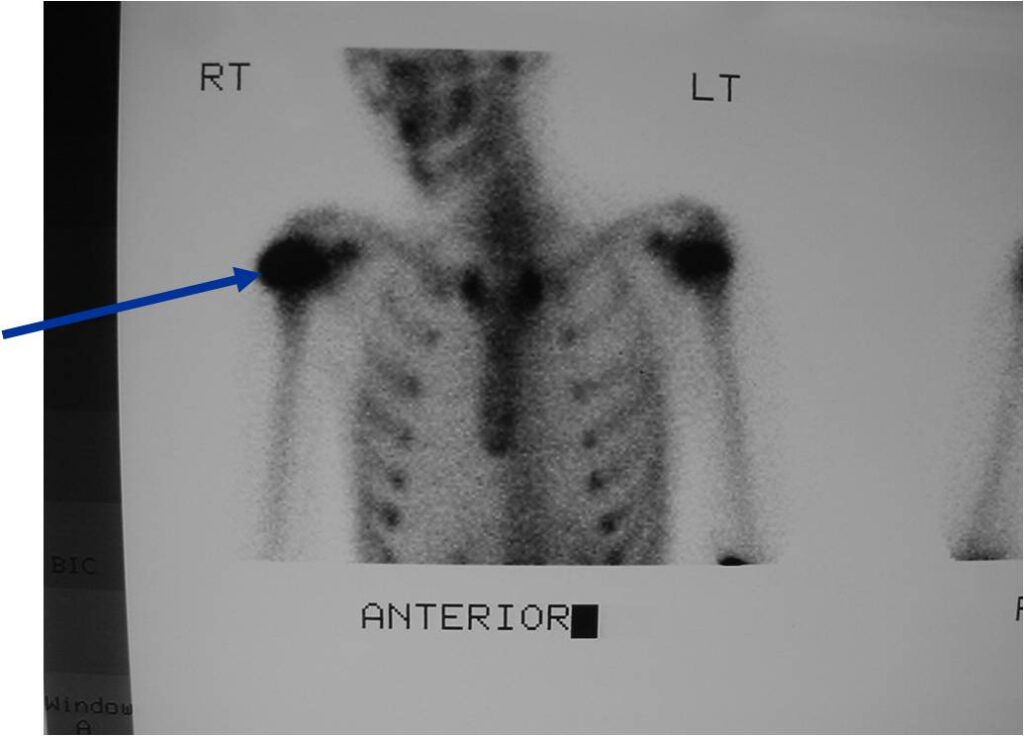

General Information Enchondroma is a benign indolent intramedullary hyaline cartilage neoplasm Accounts for 10% of all benign osseous tumors Limited growth, most lesions are less than 5 cm in maximal dimension Bones grow from a cartilaginous growth plate that...